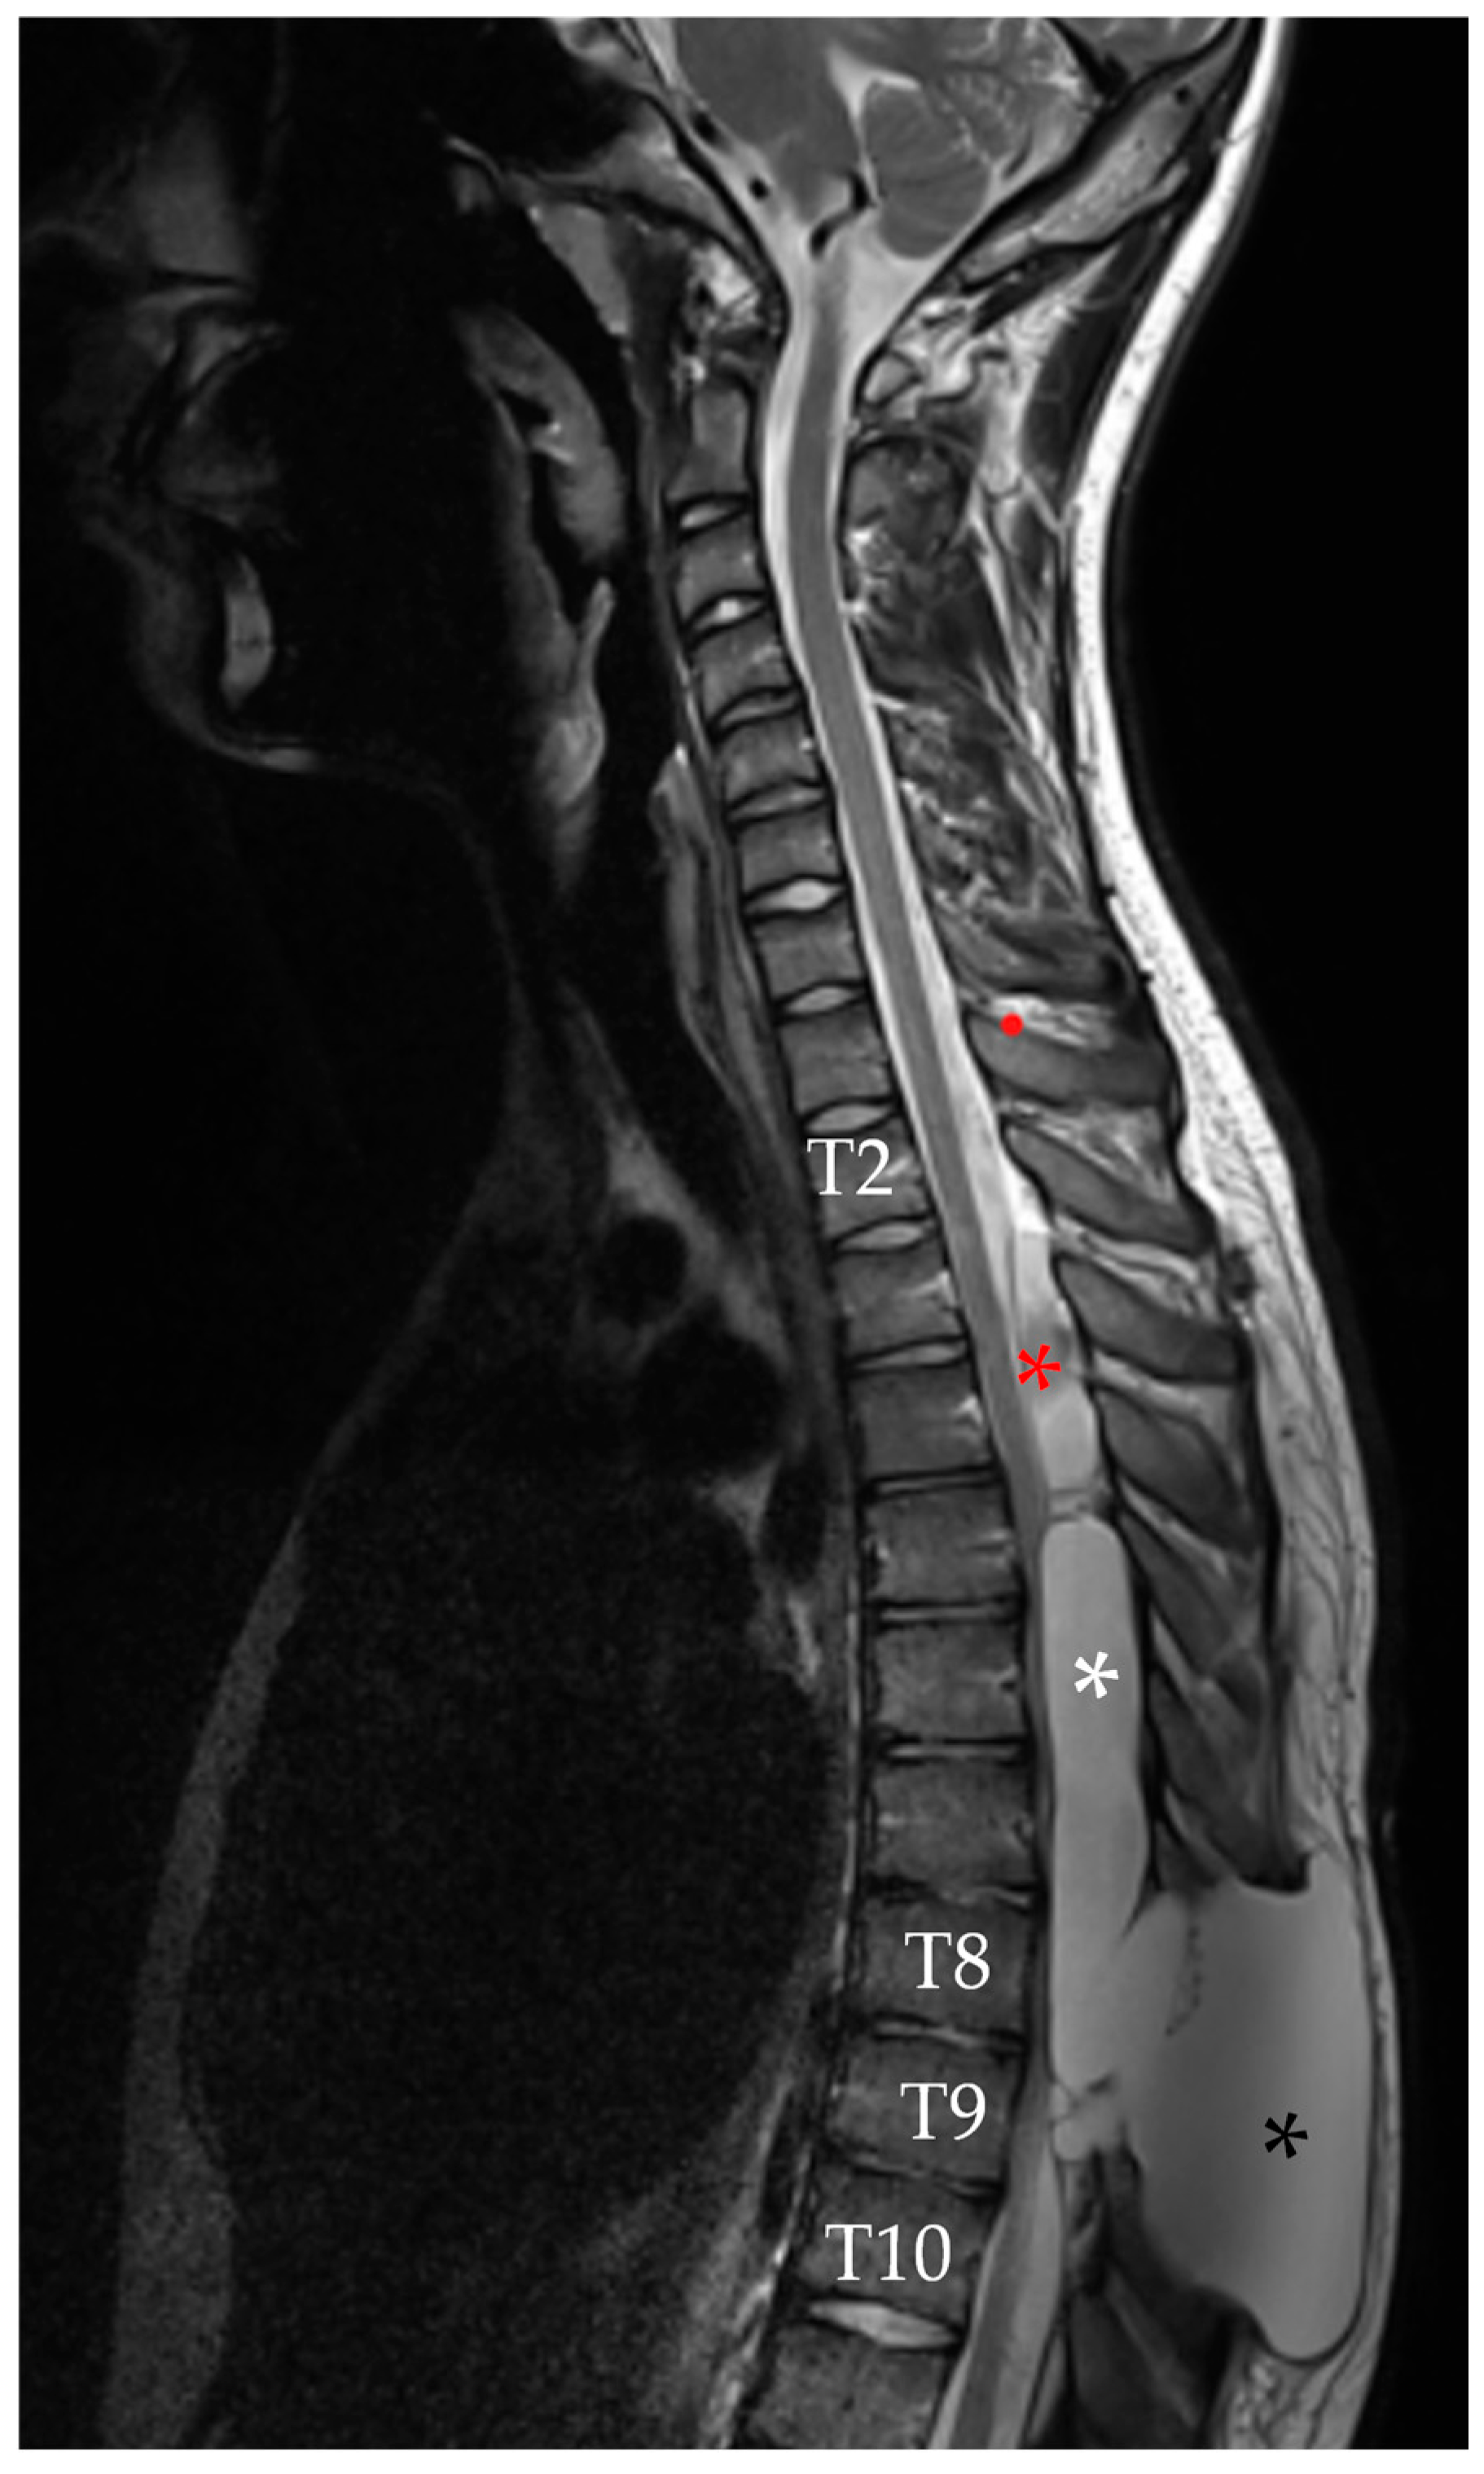

2.1. First Admission

2.2. First Follow-Up

2.3. Second Admission

2.4. Second Follow-Up